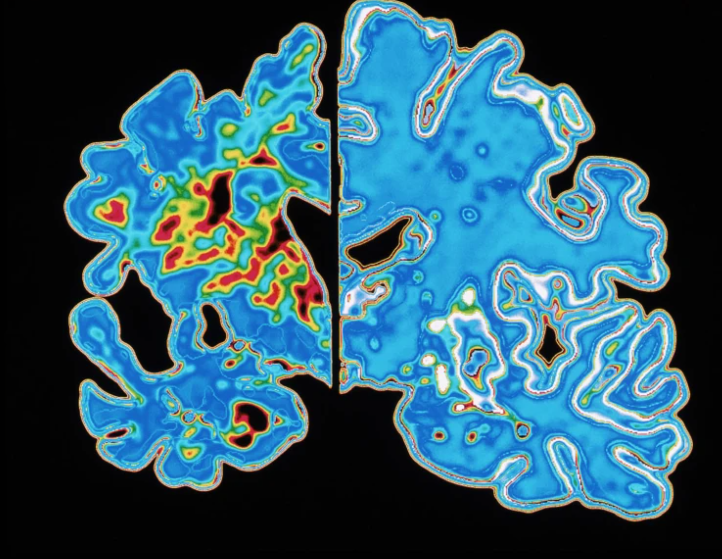

Proteinat tau jonormale mund të formojnë fibra të ngatërruara që pengojnë komunikimin midis qelizave nervore të trurit. Testet e imazherisë së trurit që zbulojnë tau-n e ngatërruar përdoren ndonjëherë gjatë diagnostikimit të Alzheimerit, dhe studime paraprake sugjerojnë se teste të tilla mund të jenë në gjendje të parashikojnë edhe kur do të shfaqen simptomat e sëmundjes. Por teknikat e imazherisë janë të ndërlikuara dhe të shtrenjta, thotë Schindler. Ndërkohë, studiuesit kanë eksploruar teste më të thjeshta, të bazuara në gjak, që mund të gjurmojnë gjithashtu proteinën tau. /skyweb.al